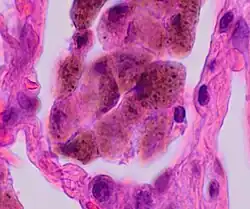

| A "smoker's macrophage", with yellow to light brown and finely granular cytoplasmic pigment. | |

Respiratory bronchiolitis is a lung disease associated with tobacco smoking.[1] In pathology, it is defined by the presence of "smoker's macrophages".[1] When manifesting significant clinical symptoms it is referred to as respiratory bronchiolitis interstitial lung disease (RB-ILD).[1]